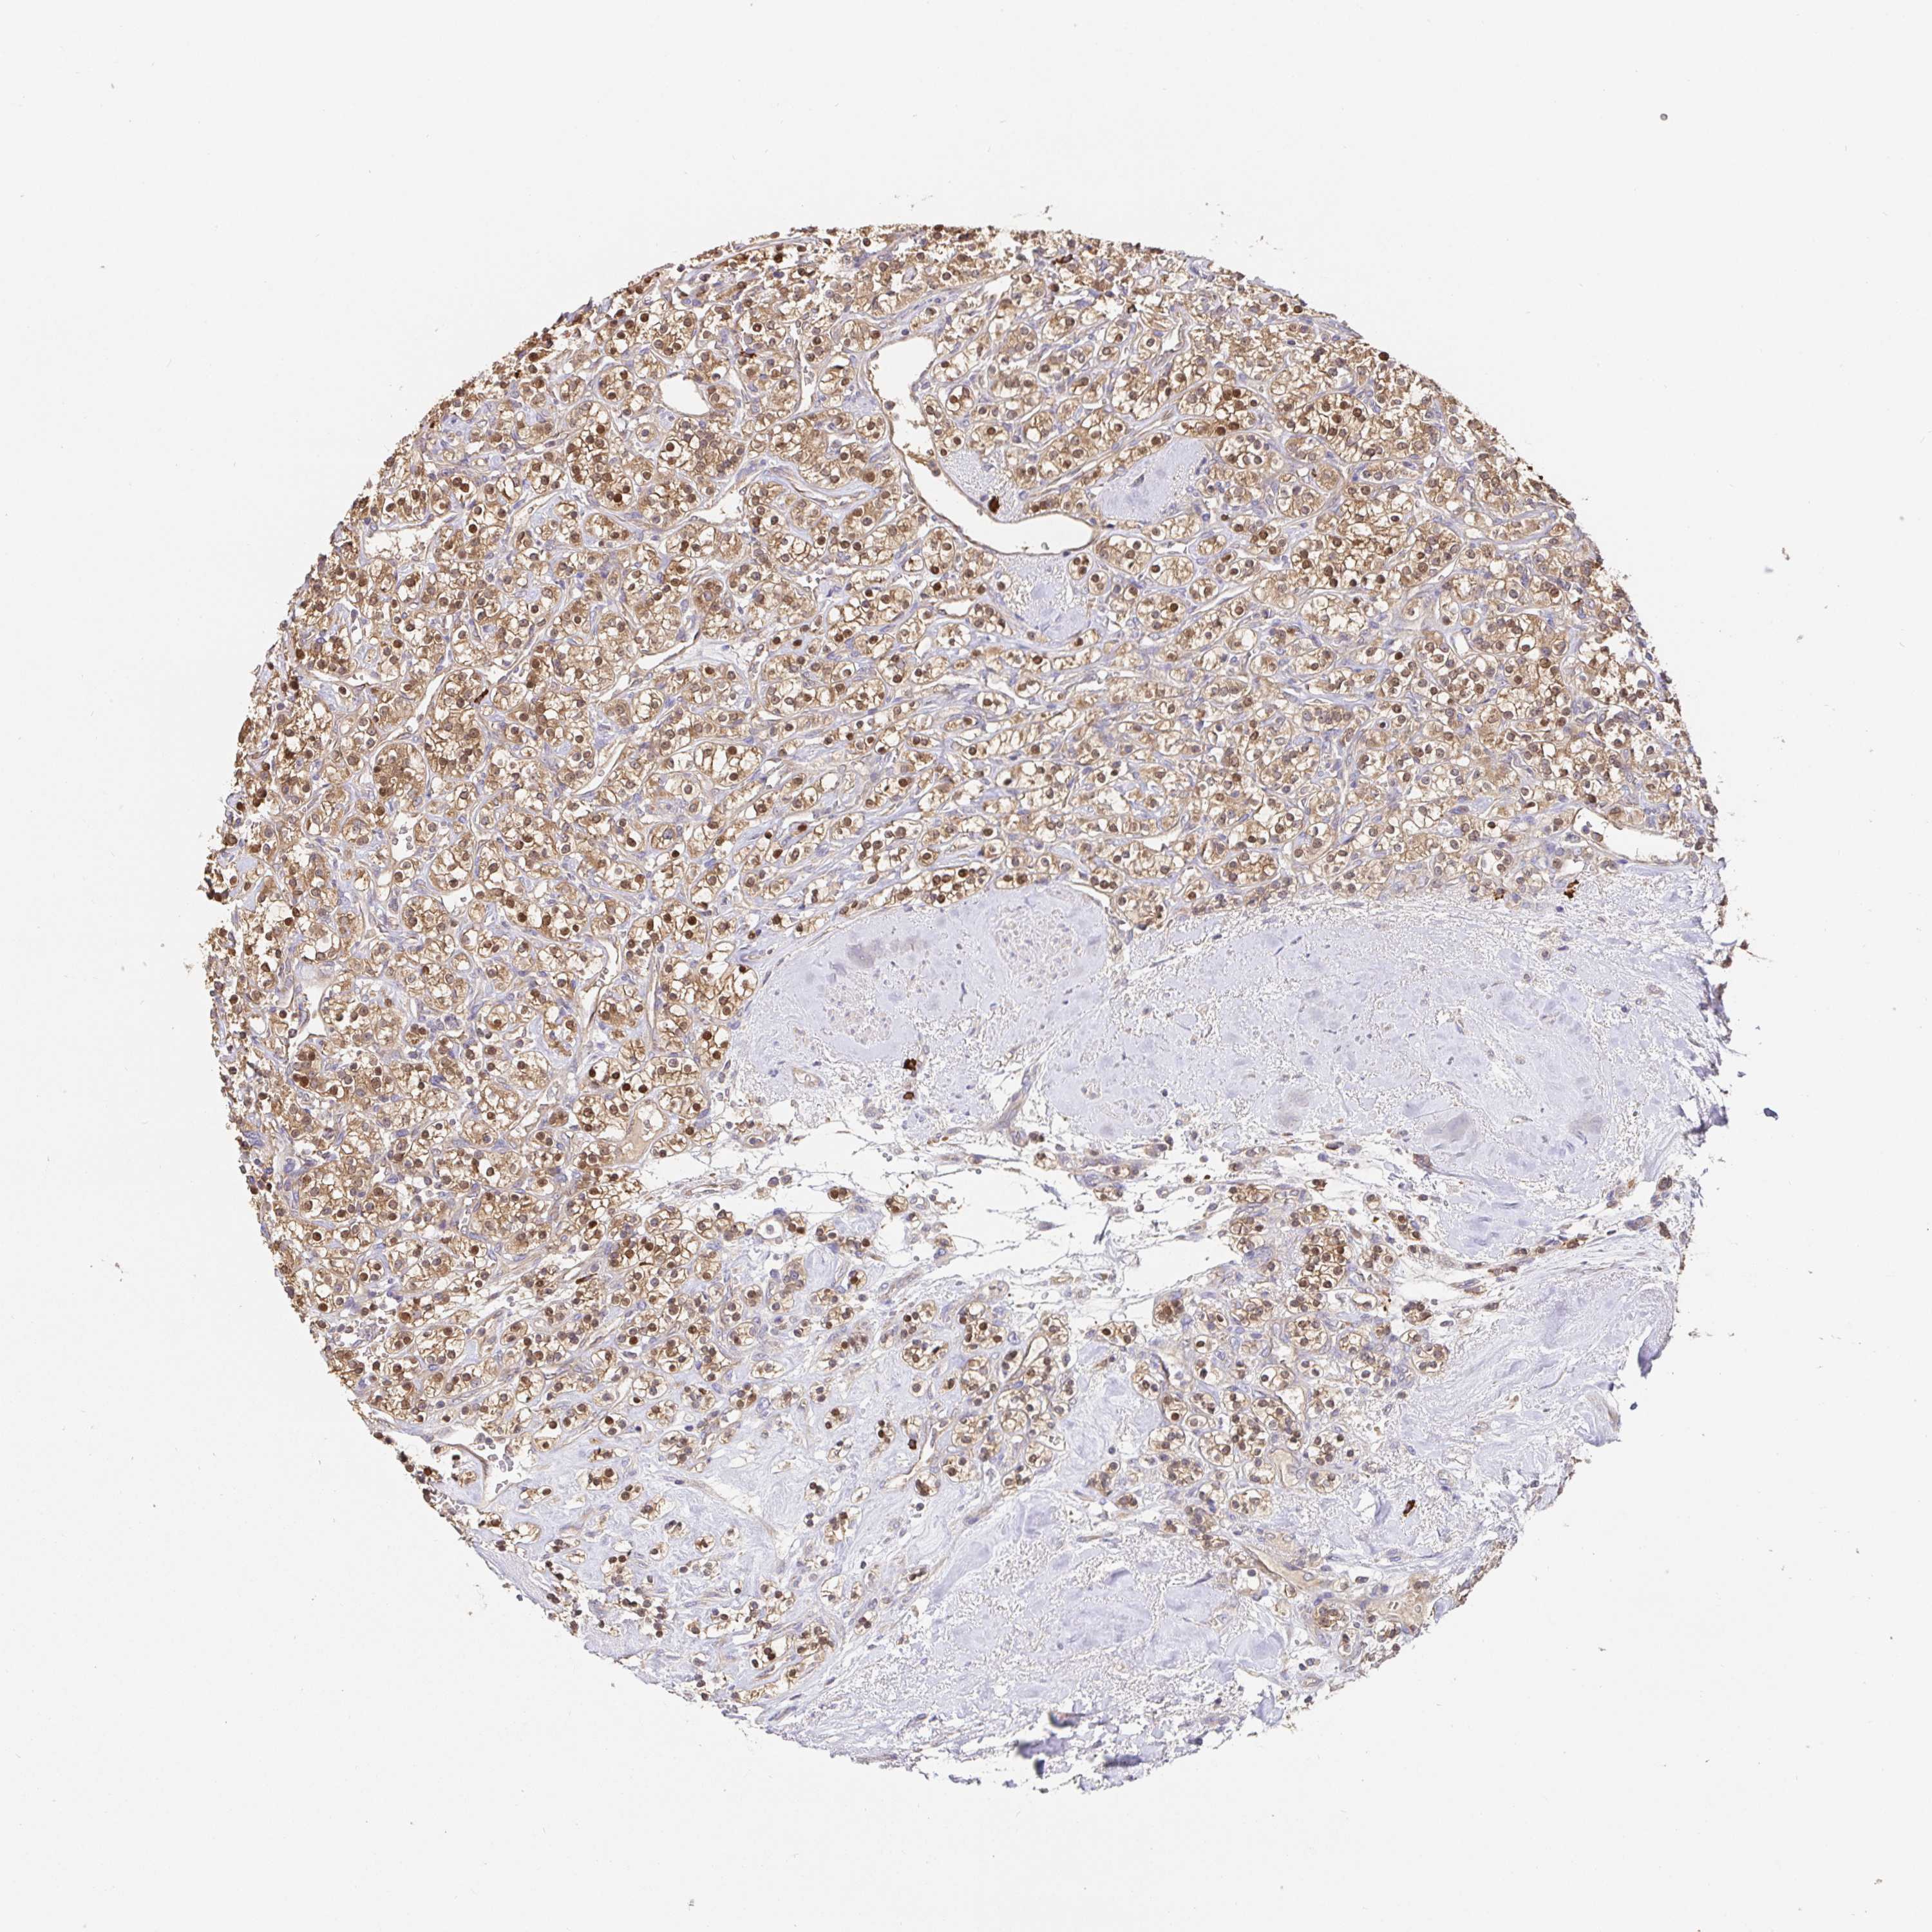

KIDNEY RENAL CLEAR CELL CARCINOMA (VALIDATION) - Interactive survival scatter ploti

The Survival Scatter plot shows the clinical status (i.e. dead or alive) for all individuals in the patient cohort, based on the same data that underlies the corresponding Kaplan-Meier plots. Patients that are alive at last time for follow-up are shown in blue and patients who have died during the study are shown in red.

The x-axis shows the expression levels (FPKM) of the investigated gene in the tumor tissue at the time of diagnosis. The y-axis shows the follow-up time after diagnosis (years). Both axes are complimented with kernel density curves demonstrating the data density over the axes. The top density plot shows the expression levels (FPKM) distribution among dead (red) and alive patients (blue). The right density plot shows the data density of the survived years of dead patients with high and low expression levels respectively, stratified using the cutoff indicated by the vertical dashed line through the Survival Scatter plot. This cutoff is automatically defined based on the FPKM cutoff that minimizes the p-score. The cutoff can be changed by dragging the vertical line or by entering a cutoff value in the square labeled "Current cut-off".

Under the Survival Scatter plot the p-score landscape (black curve; left axis) is shown together with dead median separation (red curve; right axis). Dead median separation is the difference in median mRNA expression between patients who have died with high and low expression, respectively. It is calculated as follows: median FPKM expression of dead patients with high expression - median FPKM expression of dead patients with low expression. This is intended to aid the user in visually exploring custom cutoffs and the associated p-scores and dead median separation.

Individual patient data is displayed and can be filtered by clicking on one or more of the category buttons on the top of the page. Categories describing expression level and patient information include: high, low, alive, dead, female, male and tumor stages. The scale of the x-axis can be toggled between linear and log-scale by clicking on the "x log" button. Mouse-over function shows TCGA ID, patient information and mRNA expression (FPKM) for each patient.

& Survival analysisi

Kaplan-Meier plots summarize results from analysis of correlation between mRNA expression level and patient survival. Patients were divided based on level of expression into one of the two groups "low" (under cut off) or "high" (over cut off). X-axis shows time for survival (years) and y-axis shows the probability of survival, where 1.0 corresponds to 100 percent.

HAGH is not prognostic in Kidney Renal Clear Cell Carcinoma (validation)

Best expression cut offi

Based on the FPKM value of each gene, patients were classified into two groups and association between prognosis (survival) and gene expression (FPKM) was examined. The best expression cut-off refers the FPKM value that yields maximal difference with regard to survival between the two groups at the lowest log-rank P-value. Best expression cut-off was selected based on survival analysis .

When clicking on this number, the vertical dashed line indicating cut-off, the interactive survival plot, and the Kaplan-Meier curve will be adjusted to show results based on the best expression cut-off.

: 77.08

TCGA RNA samplesi

RNA-seq data is reported as average FPKM (number Fragments Per Kilobase of exon per Million reads), generated by the The Cancer Genome Atlas (TCGA) .

Normal distribution across the dataset is visualized with box plots, shown as median and 25th and 75th percentiles. Points are displayed as outliers if they are above or below 1.5 times the interquartile range. FPKM values of the individual samples are presented next to the box plot.

Average pTPM 64.6

Number of samples 100